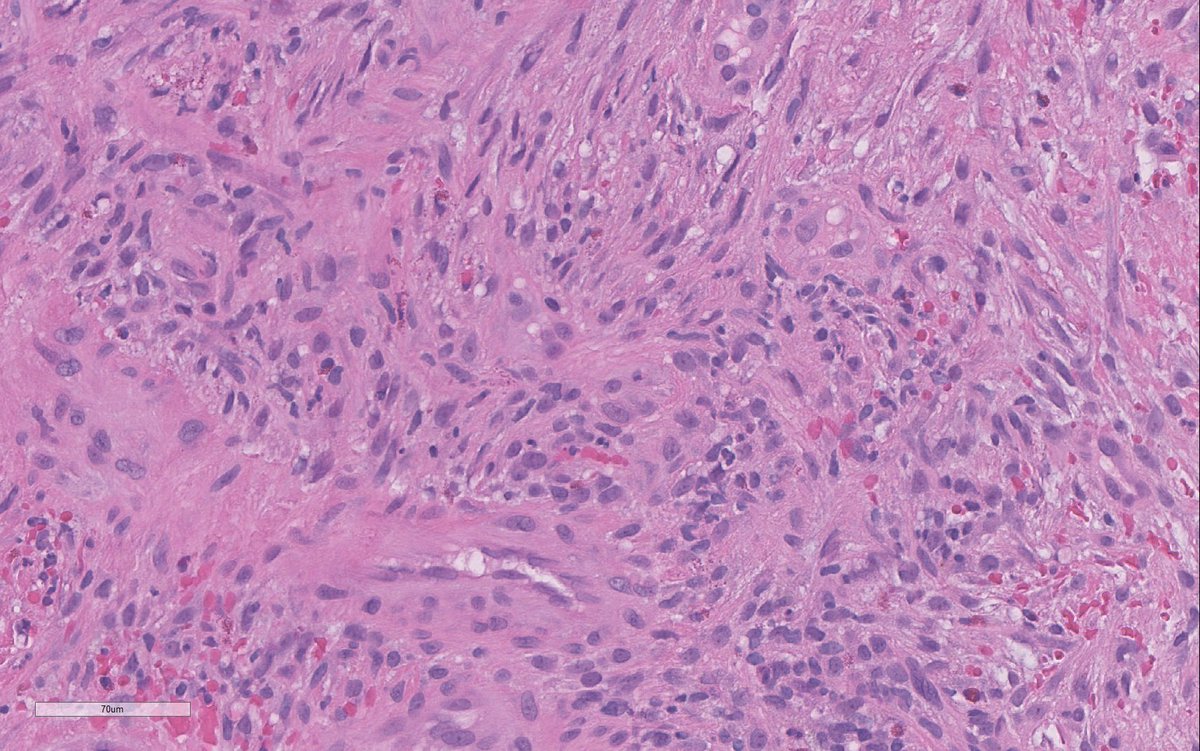

Happy to share our work with @OwkinScience on a daring challenge: Can #PDAC epithelial and stromal molecular phenotypes be identified from standard histology slides? Better yet, can this help resolve intra-tumor heterogeneity? a thread 🧵 nature.com/articles/s4146…